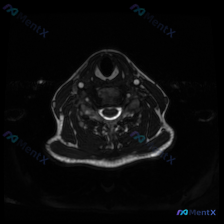

刚看到一个有意思的读片病例,用户提供了一张颈椎MRI-T2序列轴位图像,明确提问是围绕「椎间盘病变」的观察,整理一下完整分析思路分享给大家。

这是颈椎中下段的MRI-T2加权轴位图像,我们先按层次梳理客观观察结果:

- 椎管与脊髓:脊髓位于椎管中央,形态规则,内部信号没有异常高/低信号灶,周围脑脊液信号正常,硬膜囊没有受压变形

- 椎骨与椎间盘:椎体前缘平整,骨髓信号正常,后方附件结构对称,没有骨质增生或狭窄;椎间盘后缘和硬膜囊前缘界限清晰,没有椎间盘突出、膨出或脱出的征象

- 椎旁软组织:双侧颈动静脉流空信号正常,气管食管位置形态正常,颈部肌群对称信号均匀,双侧甲状腺信号均匀,没有异常占位

二、核心客观结论

就这张单个层面的轴位图像来说:没有发现任何支持椎间盘病变的影像学证据,本层面所有结构的信号和形态都符合正常表现。